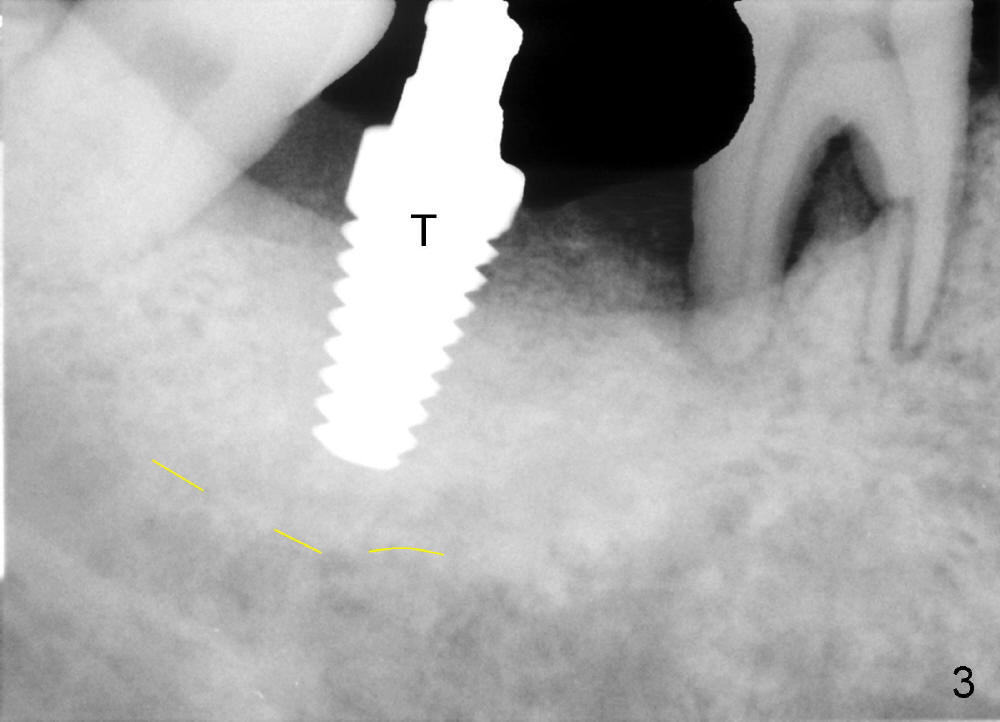

Luckily the patient returns for #31 implantation 4 months post socket preservation. Bone forms in the alveolus and above (Fig.1 black and white arrowheads, respectively). A 6 mm tissue punch is used to open the wound (Fig.2). Osteotomy forms using bone expanders, reamers and taps (Fig.3: 6x14 mm tap). Without infection, local anesthesia is more easily achieved than immediate implant when infection exists. The depth is controlled more readily with delayed implantation. Following adjustment of trajectory, a 7x11 mm implant is placed with insertion torque 60 Ncm (Fig.4 I). Fig.5 shows that the implant obliterates the wound; an abutment (A) is placed to retain perio dressing. With formation of new bone from socket preservation, insertion torque seems to be more easily obtained with the short implant. There is no space to re-use the harvested bone (Fig.6). The implant remains stable postop. Apparent new bone is forming toward the distal coronal threads 5 months postop (Fig.7). The bone around the implant remains stable 17 months post cementation (Fig.8), although there is an episode infection at the neighboring tooth (#30). The patient is more eager to have implants for the maxilla, since the flipper has lost. After implant placement at #7, the pain at #30 becomes more severe.